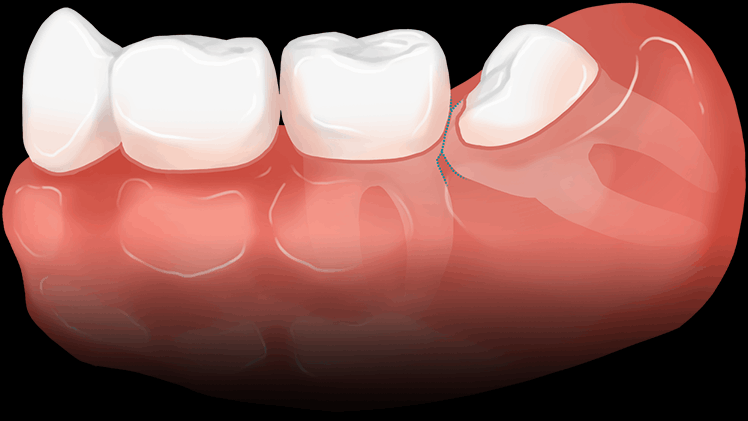

사랑니가 잇몸에 덮여있어 일부만 보이는 경우 치아와 잇몸사이에 세균이 서식하여 충치 및 염증을 일으킬 가능성이 높습니다.

드물게 치관부를 만드는 조직에서 물혹이 형성될 수 있습니다. 커지게 되면 신경마비 및 턱뼈가 부러질 위험이 있습니다.

수평으로 누운 매복사랑니는 바로 절단한 후에

남아있는 치아를 파절시켜서 제거합니다.

매복사랑니 발치 후